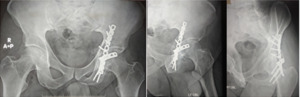

Eighteen patients were fixed with one spring plate, six patients were fixed with two spring plates, and all of them were reinforced with a 3.5mm reconstruction plate [Figure 2].

Immediate postoperative radiographs were used to judge the precision of the reduction [Figure 3]. Follow-up radiographs were taken regularly in the outpatient clinic to detect any reduction changes. The displacement of 0 to1 mm was considered anatomical, the displacement of 2 to 3 mm was considered good, and displacement >3 mm was considered unsatisfactory [Figure 4].